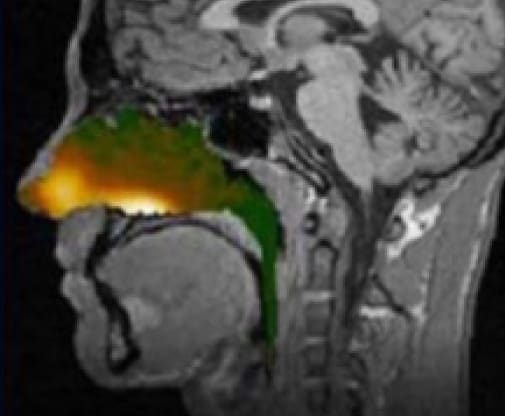

The Nasax® proprietary powder formulation for intranasal delivery is comprised of uniform-sized spherical API and a carrier approved for inhalation. The technology enables a rapid and precise delivery of the drug to the bloodstream and brain. Stability data demonstrate the potential for a longer shelf life and other advantages versus liquid formulations.